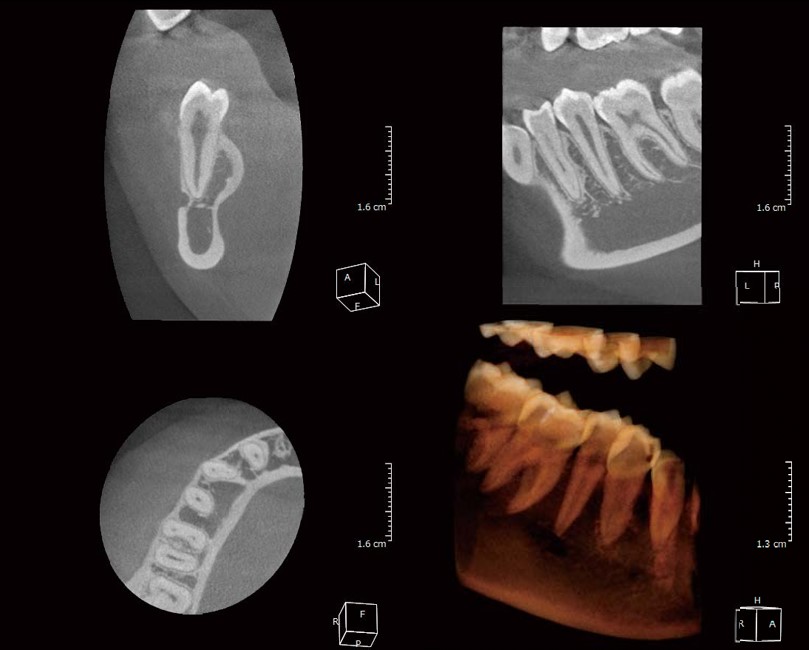

- Cung cấp hình ảnh 2D hoặc 3D (tùy thiết bị) mang đến cho Bác Sĩ cái nhìn trực quan, rõ ràng.

Hình ảnh chụp toàn hàm từ X-ERA Smart